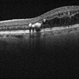

- 66-year-old white male, former smoker, with a history of femoral artery stent a plaque removal in 2017, triple bypass 2019 (at that time there was no high grade carotid stenosis), diabetes significant for SNPDR OD and PDR OS (NVD). He underwent PRP OS and two months later developed a vitreous hemorrhage and had a PPV OS. Early in the post-operative period vision dropped to LP due to acute CRAO with retinal embolus present. He was found to have progressed to high grade carotid stenosis (versus imaging 6 months ago) and a left carotid endarterectomy was performed (see picture of the large plaque) .